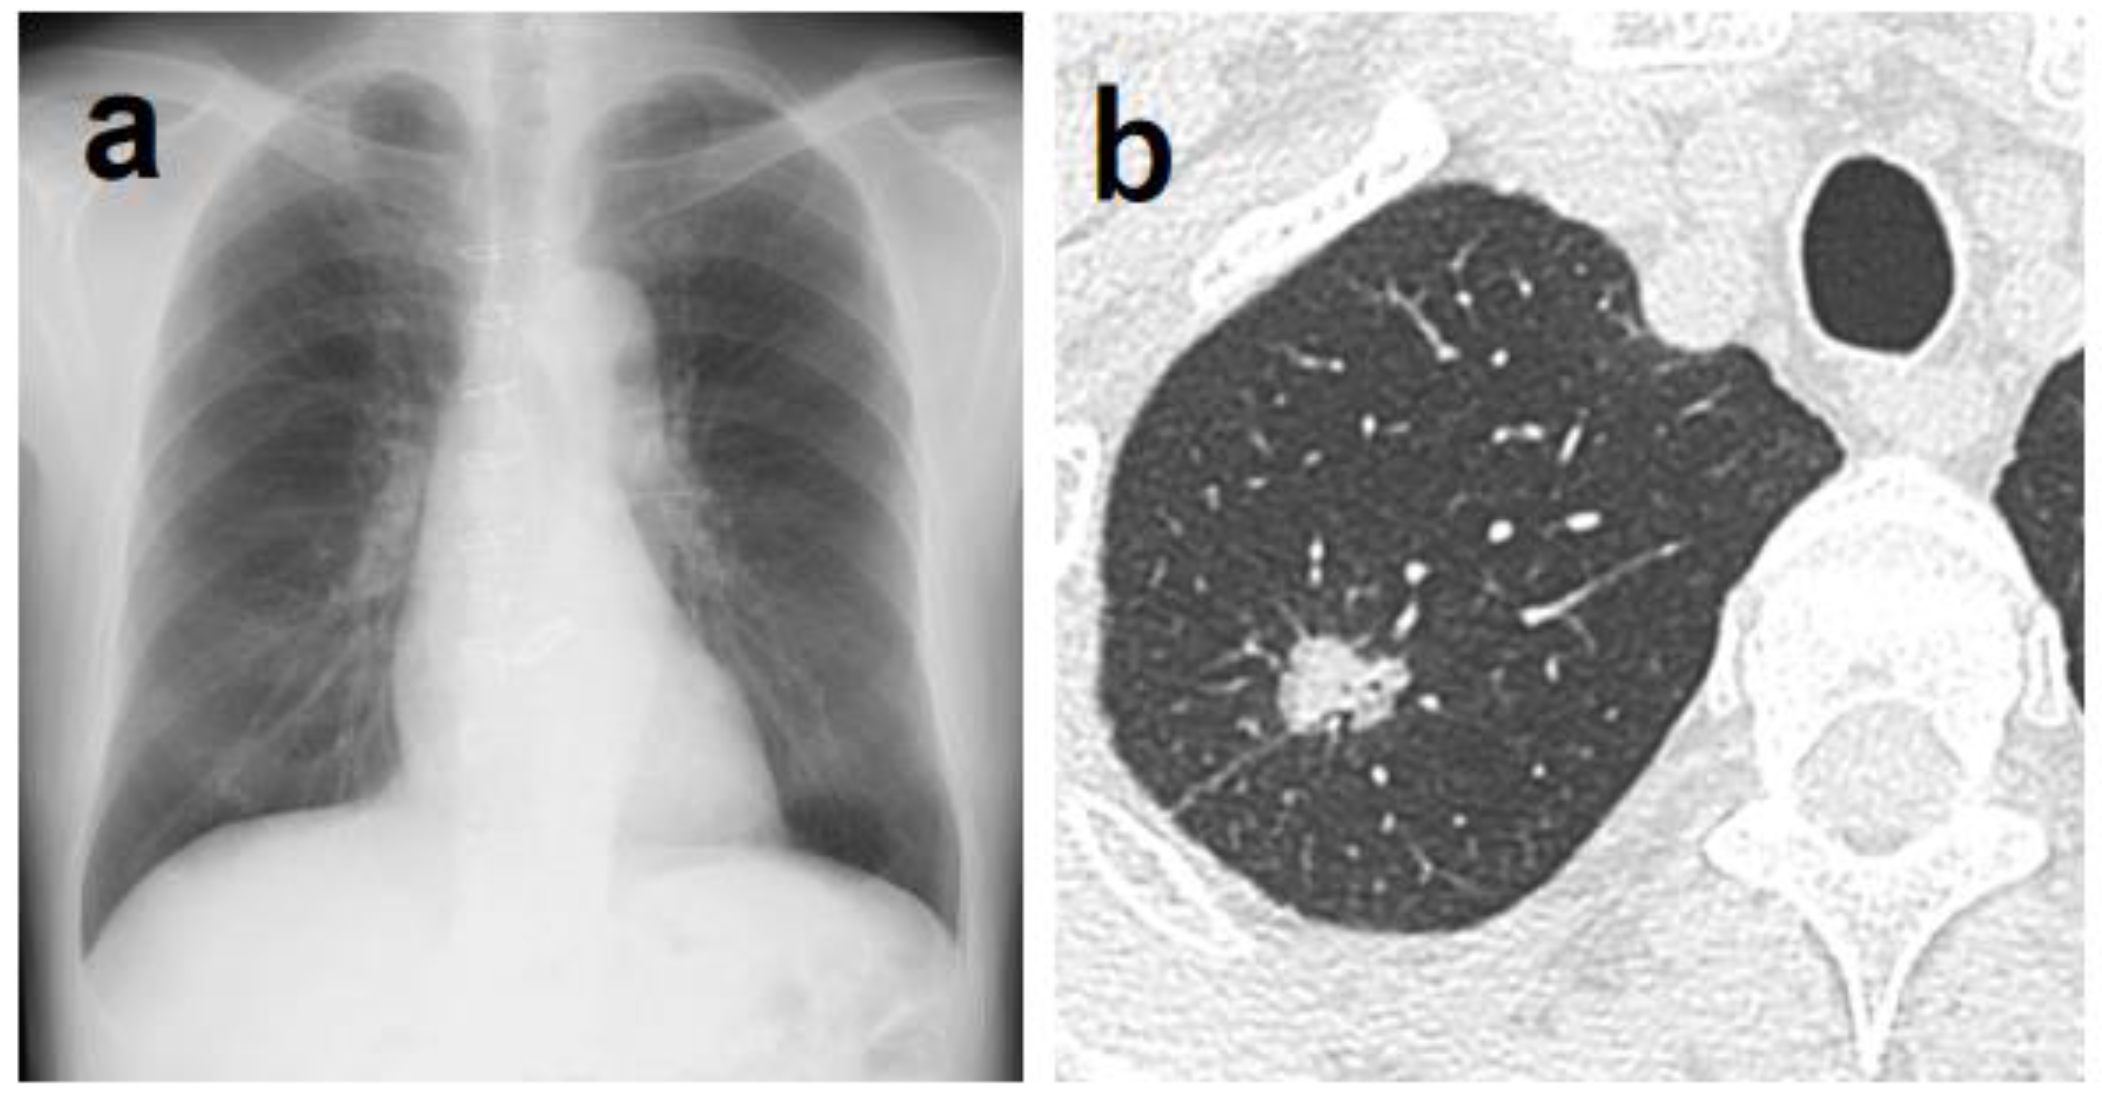

Figure 1. (1a) A shadow overlapping the clavicle in the right upper lung field that could not be determined by AI. (1b) Chest CT showing a mass with a total size of 4.3 cm and a solid size of 2.1 cm in the right S1 region. The histopathological diagnosis was adenocarcinoma (lepidic adenocarcinoma), total tumor and invasive size of 1.7 cm, pT1bN1M0 (stage IIB). (2a) A shadow overlapping the clavicle in the right upper lung field that could not be pointed out by AI diagnosis. (2b) Chest CT showing a nodule with a total and solid size of 1.6 cm in the right S1 region. The histopathological diagnosis was adenocarcinoma (lepidic adenocarcinoma), tumor total and invasive size 1.7 cm, pT1bN1M0 (stage IIB). (3a) A shadow that could not be determined by AI despite being a large tumor of 4 cm in diameter. A shadow running parallel to the blood vessels, partially overlapping the heart shadow in the left lower lung field. (3b) Chest CT showing a mass with a total and solid size of 4.3 cm in the left S8–9 region. The histopathological diagnosis was adenoid cystic carcinoma, total tumor and invasive size of 4.0 cm, pT2aN0M0 (stage IB).

The main reasons why lung tumors could not be detected by the AI in 84 cases are listed in Table 2. Thirty-five cases had lesions overlapping with anatomical structures, such as the mediastinum, heart, and clavicle, or lesions below the diaphragm. Eight of these 35 cases were detectable by physicians (Figure 1). Conversely, there was one case in which it was difficult for physicians to detect the shadow overlapping the anatomical structures, but it was detected by AI (Figure 2). Eighteen cases were AIS, thirteen were lepidic adenocarcinoma (invasive size: 0.05–2.0 cm), and six were small nodules less than 0.7 cm in diameter. The other six cases were difficult to visualize on chest radiographs. Of these six cases, three cases had ground-glass components as the main component on CT, and one case had nodule and pulmonary vessels visible in succession. Many of these lesions were difficult to visualize due to the imaging conditions. Six patients did not fit these conditions; their lesions could be determined by physician interpretation, and their non-detection was judged to be an oversight by the AI (Figure 3).